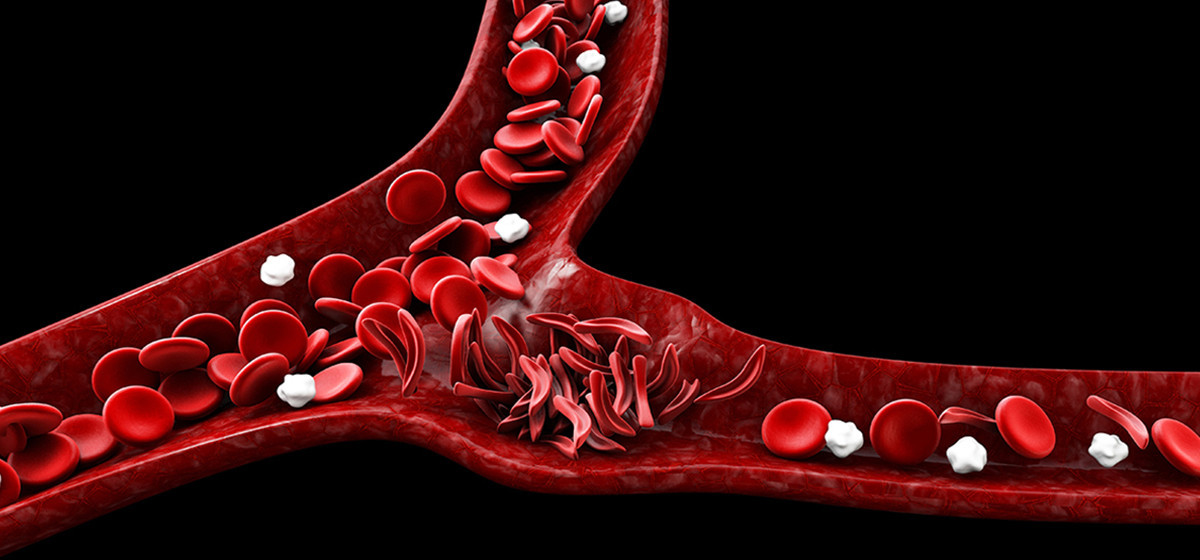

थारू समुदायमा रहेको वंशाणुगत रोग ‘सिकलसेल एनिमिया’ पहिचानका लागि रगत परीक्षणलाई उच्च प्राथमिता दिइएको छ । स्वास्थ्य कार्यालयका सिकलसेल एनिमिया तथा थालेसिमिया रोगसम्बन्धी स्रोत व्यक्ति सिद्धराज भट्टले थारु समुदायको बाहुल्यता रहेका पालिकामा रगत परीक्षण शिविर नै सञ्चालन गरिएको जानकारी दिनुभयो । उहाँका अनुसार कञ्चनपुरको बेलडाँडी गाउँपालिकामा दुई हजार चार सय दुई जनाको रगत परीक्षण गर्दा दुई सय २९ पोजेटिभ पत्ता लागेको जानकारी दिनुभयो । उनीहरुको अन्तिम परीक्षण गर्दा दुई सय १३ जना सिकलसेल बाहक १० जनामा थालेसिमिया र ६ जना सिकलसेल रोगी पत्ता लागेका छन् । पूनर्वास नगरपालिकामा ९ सय ७६ जनाको रगत परिक्षण गर्दा ९८ जनामा पोजेटिभ देखिएको थियो । जसको अन्तिम परीक्षण गर्दा ७९ जनामा बाहक (ट्रेट)देखा परेको थियो । एक सय ११ जनामा ट्रेटसँगै विटा थालेसिमिया र तीन जनामा विटा थालेसिमिया होमोजाइगोस पत्ता लागेको थियो । त्यसैगरी भीमदत्त नगरपालिकामा आठ सय ६६ जनाको रगत परीक्षण गर्दा ९९ जना पोजेटिभ भेटिएका छन् ।

जसको अन्तिम परीक्षण गर्दा ७७ जना सिकलसेल ट्रेट, १८ जना सिकलसेल ट्रेटसँगै बिटा थालेसिमिया र चार जनामा सिकलसेल पत्ता लागेको थियो । स्वास्थ्य कार्यालयले थारु समुदायमै गएर स्क्रिनिङ टेस्ट गरेको थियो । स्क्रिनिङ टेष्टमा पोजेटिभ देखिएका व्यक्तिको प्रदेश जनस्वास्थ्य प्रयोगशालामा नमूना लगेर परीक्षण गरिएको थियो । थारु समुदायको बाहुल्यता भएको बेलौरी नगरपालिकामा एक हजार तीन सय जनाको रगत परीक्षण गरिएको थियो । जसमा एक सय १४ जना पोजेटिभ देखिएका थिए । अन्तिम परीक्षण गर्दा एक सय ३२ जनामा सिकलसेल बाहक, पाँच जनामा थालेसिमिया र पाँच जना सिकलसेल रोगी पत्ता लागेका थिए । स्वास्थ्य कार्यालयका सिकलसेल एनिमिया तथा थालेसिमिया रोगसम्बन्धी स्रोत व्यक्ति सिद्धराज भट्टका अनुसार कञ्चनपुरको विभिन्न पालिकामा स्क्रिनिङ टेष्ट गरिएको बताउनुभयो । “बाहक (ट्रेट) देखा परेकाहरुको रगतको अन्तिम चेक गर्दा धेरैमा सिकलसेल एनिमिया भएको पुष्टि भएको छ ।” भट्टले भन्नुभयो–“हरेक एक सयजनाको परीक्षणमा आठ जना बिरामी देखिएका छन ।”

उहाँले बाहक(ट्रेट) देखा परेका महिला पुरुषले विवाह गर्दा रगत परीक्षण गरेर मात्रै गर्नुपर्ने बताउनुभयो । “बाहक(ट्रेट) देखा परेका महिला पुरुषले विवाह गरे उहाँहरुबाट जन्मिने व्यक्ति पनि रोगी जन्मन्छ ।” उहाँले भन्नुभयो–“त्यसैले विवाह गर्नुभन्दा पहिले रगत परीक्षण गरेर मात्रै विवाह गर्नु उपयुक्त हुन्छ ।” हेमोग्लोबिनसँग सम्बन्धित खराबीको कारणले हुने समस्या विश्वमा ५ प्रतिशत भन्दा बढी भएको तथ्याङ्क छ । तीमध्ये सबै भन्दाबढी देखापरेको समस्या सिकलसेल एनिमिया र थालेसिमिया रहेको उहाँको भनाइ छ । नेपालमा पनि खासगरी थारु चौधरी समुदायमा यो रोगको प्रकोप उच्च रहेको स्वास्थ्य कार्यालयले जनाएको छ । केही समयअघि नेपाल सरकार, स्वास्थ्य अनुसन्धान परिषद्सँग त्रिभुवन विश्वविद्यालय ट्रफल अनुसन्धान प्रयोगशालाले गरेको अनुसन्धानमा पश्चिम नेपालका अविवाहित थारु समुदायका महिलाको डीएनए परीक्षण गर्दा १८ प्रतिशत व्यक्तिमा सिकलसेल हेटरोजाइगस ट्रेट रहेको पाइएको उहाँले बताउनुभयो ।

थारु चौधरी समुदायमा यो रोग एउटा प्रमुख जनस्वास्थ्य समस्याको रुपमा रहेको र समयमै यसको रोकथामका उपाय अवलम्बन गर्न नसकिए अवस्था झन भयावह हुनसक्ने भएकाले कञ्चनपुरका थारु चौधरी समुदायको बसोबास उच्च रहेका पालिकामा यो रोगको पहिचान तथा निदानको लागि स्वास्थ्य कार्यालयले रगत परीक्षण गरेको भट्ट बताउँनुहुन्छ । “सिकल सेल एनिमिया र थालेस्मिया व्यक्तिको जिन सम्बन्धी खराबीको कारणले हुन्छ रोगसँग सम्बन्धित सानो खराबी भएको अवस्थालाई ट्रेट भनिन्छ ।” भट्टले भन्नुभयो–“केटा मान्छेमा ट्रेट छ र उसको विवाह ट्रेट भएको केटी मान्छेसँग भयो भने त्यसबाट जन्मने २५ प्रतिशत बच्चाहरुमा सिकल सेल रोग भएर जन्मने गर्छन ।” ट्रेट भएको व्यक्तिलाई शारीरिक रुपमा खासै समस्या नदेखिने र समस्या देखिए पनि सामान्य खालको हुने उहाँले बताउनुभयो । सिकलसेल रोग भएमा थकाइ लाग्ने, श्वास प्रश्वासमा समस्या हुने, छाती, पेट, हातखुट्टाको कुर्कुच्चा दुख्ने, आँखामा समस्या देखापर्ने, ज्वरो आउने, बान्ता हुने, खोकी लाग्ने लक्षण देखापर्ने गर्दछन ।